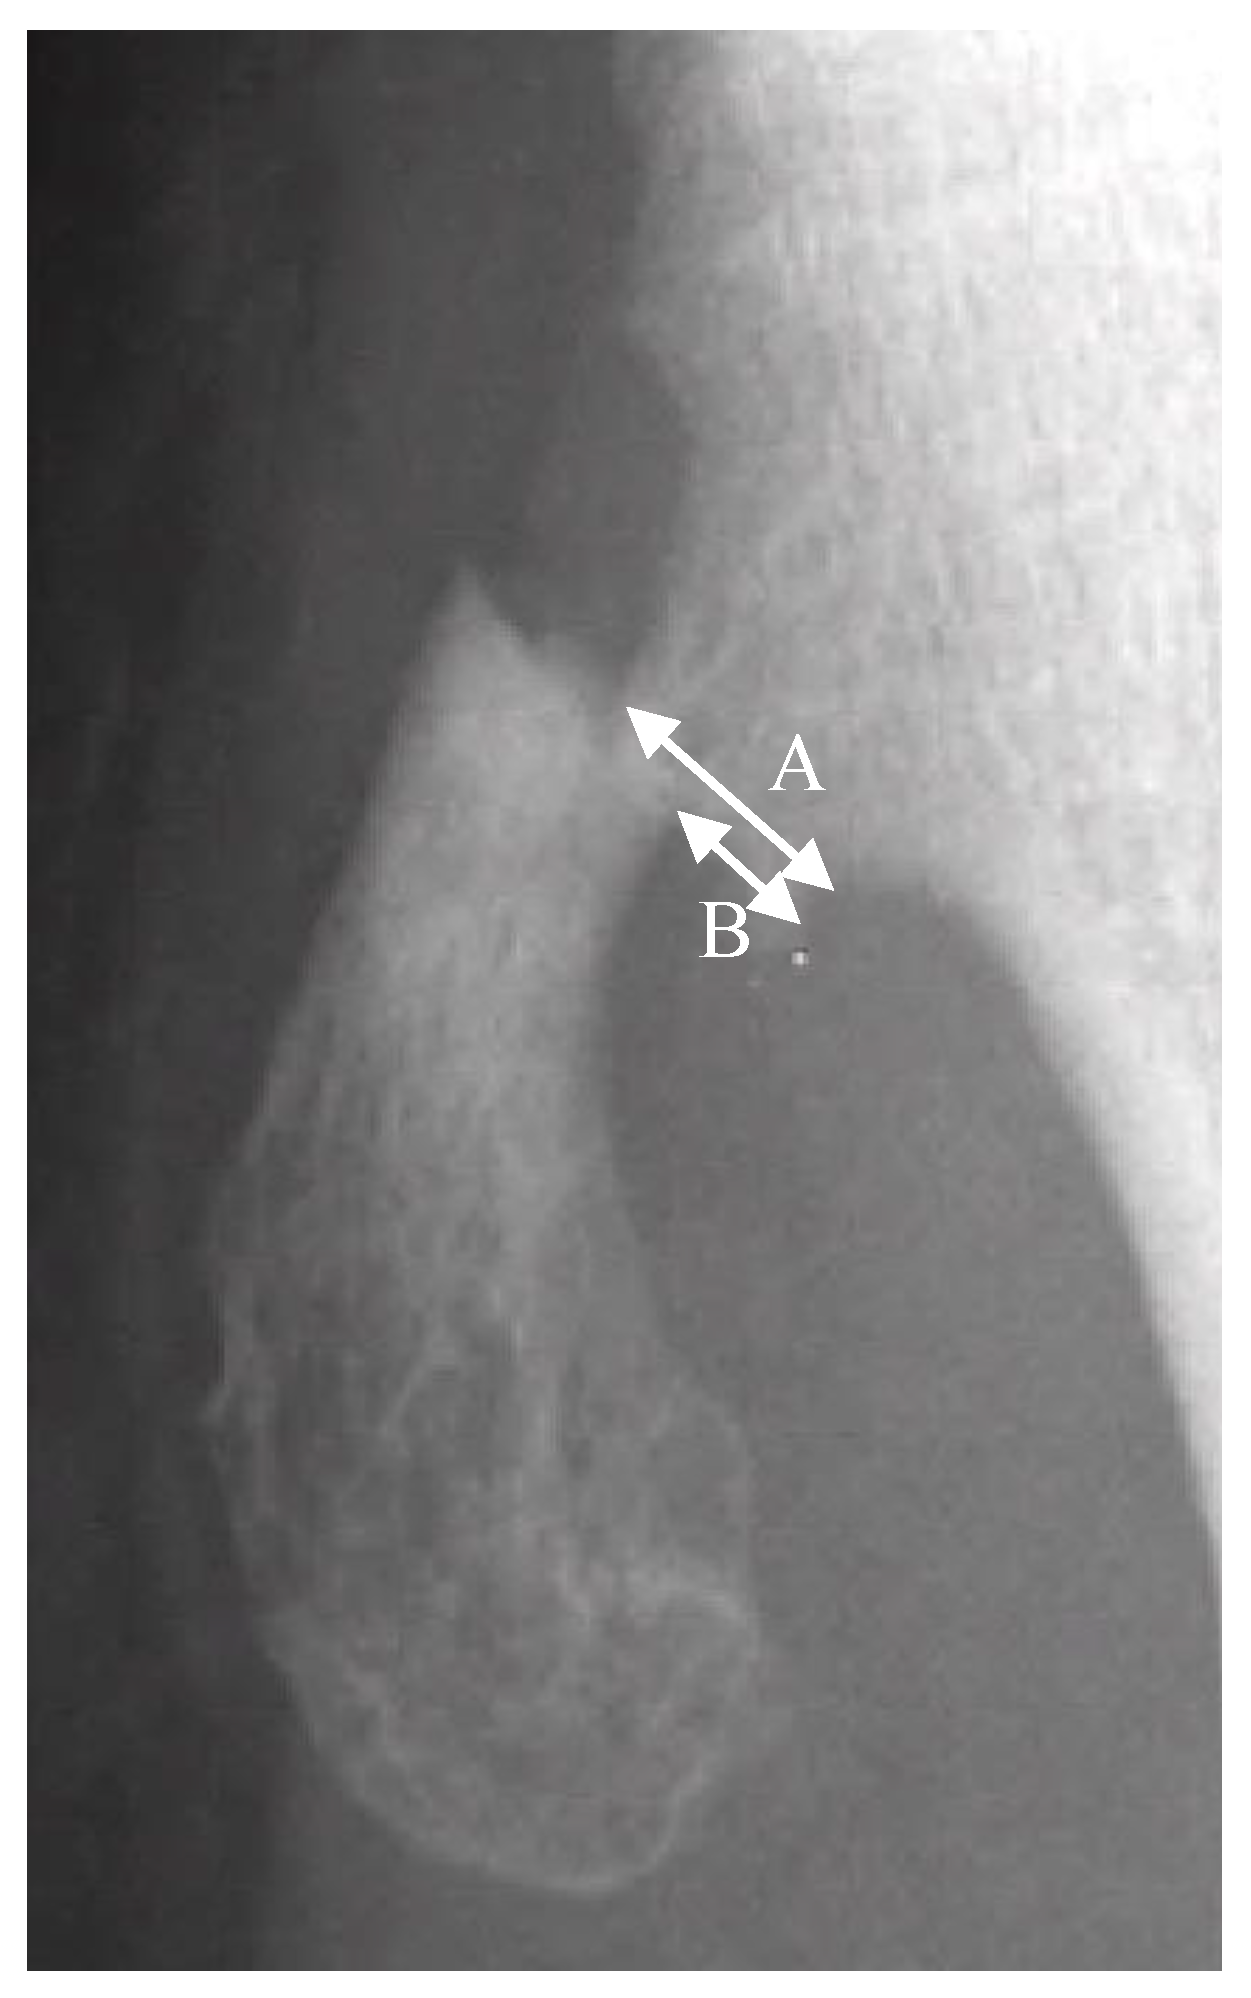

Figure 1. A is the width of the proximal fragment of the fractured osteochondroma. B is the displaced distance of the distal fragment in relation to the proximal fragment. Translation is defined by the equation of B/A × 100%.

The fractures of the osteochondromas were divided into two types: displacement and non-displacement. In the present study, displacement was defined as a gap widening of more than 1 mm between fragments, or translation of more than 50% of the distal fragment in relation to the proximal fragment, either by anteroposterior, lateral, or oblique radiographic views of the knee joint (Figure 1). There were 12 patients in the displacement group and 11 patients in the non-displacement group (Figure 2).